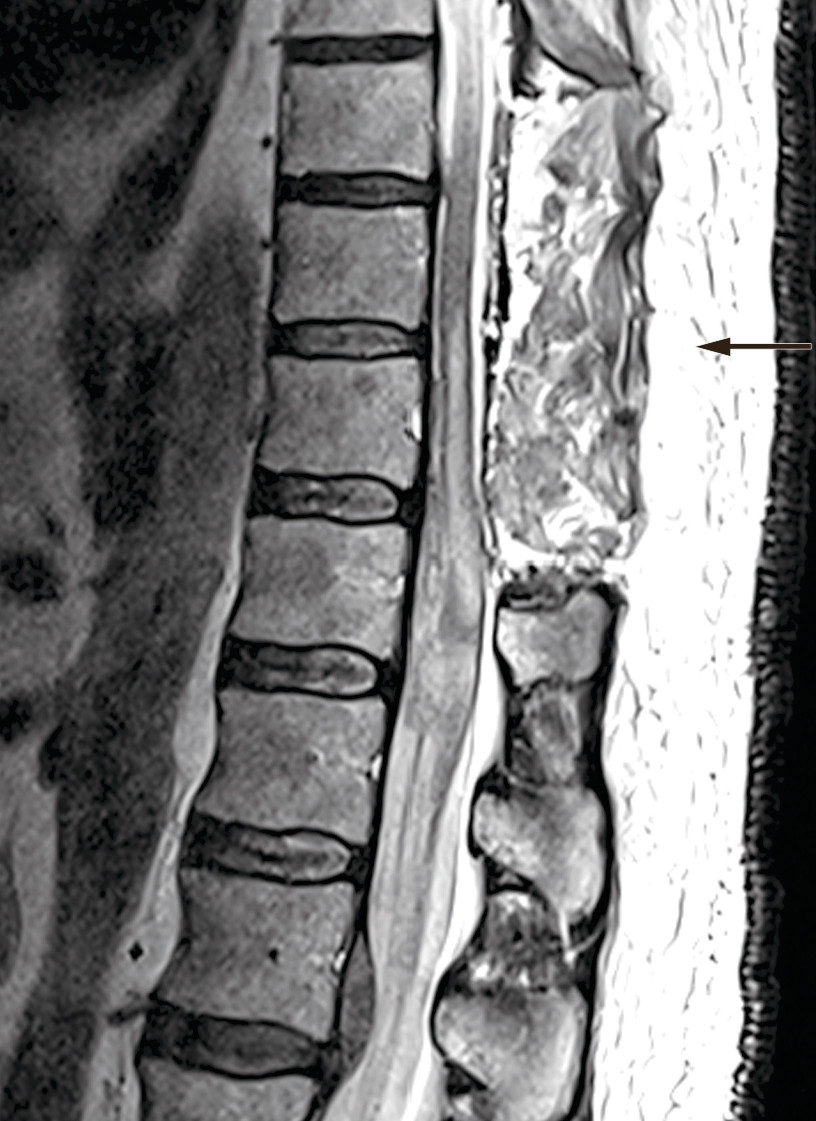

The patient showed no improvement in neurological status postoperatively. Treatment with dalteparin (Fragmin, 5 000 IU subcutaneously × 1) was started on postoperative day one, and he received standard treatment in intensive care with mean arterial pressure (MAP) above 85 mm Hg the first week (7). MRI was repeated after ten days and showed a new epidural cerebrospinal fluid accumulation at level Th10–11 with compression of the spinal cord (Figure 3). MRI of the head was also performed on account of headache and nausea. This showed a small amount of intraventricular and subarachnoid blood, which was interpreted as having spread from the spinal cord haemorrhage.